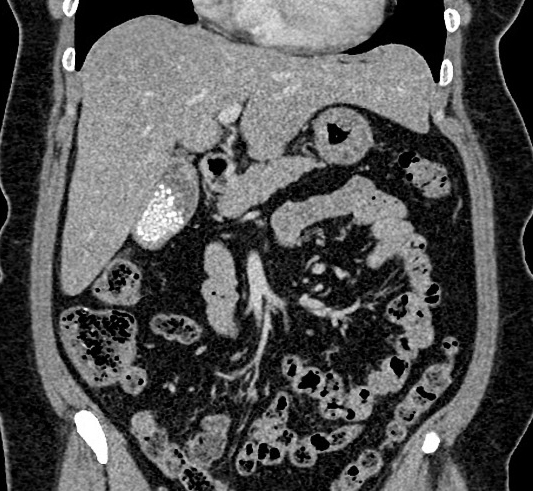

Image IRM et

cholangio -IRM ( MRCP ) : Image de calcul

de la vesicule biliaire est lacule a hyposignal dans

la vesicule remplie de liquide hyperintense

Calcule vesicule biliaire

hypointense a infundibulum de la vesicule

hyperintense . Image IRM ponderee en T2 coupe axiale

|

Image radiologique

cholangio -IRM : Image de la lithiase est lacule

hypointense a interieure la vesicule remplie de bile

hyperintense . Voie biliaire pricipale , voie

intrahepatique et canal de Wirsung en voyait

complete et nette |